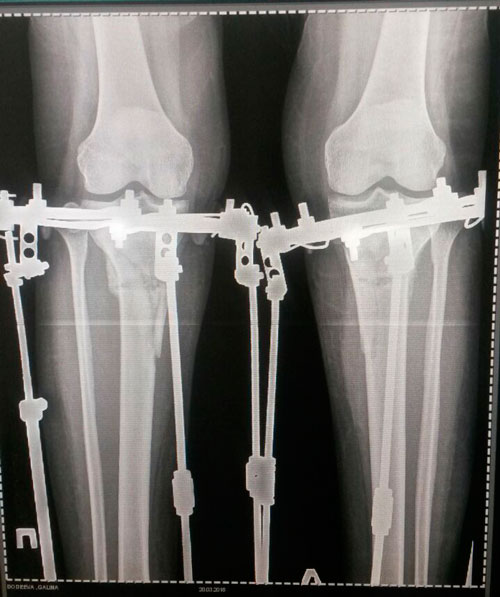

Дата операции 15.01.2018г.

Дата снятия аппаратов 23.04.2018г.

Срок лечения 97 дней.